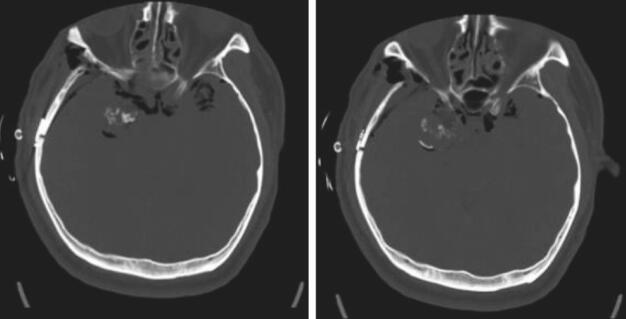

入院完善各项术前准备后行开颅肿瘤切除术,肿瘤达部分切除。术后患者恢复较好,无明显神经功能缺失。术后第一天CT(图2)示肿瘤部分切除。术后病理可见骨小梁(图3),病理报告为高分化软骨肉瘤。

图2术后第一天CT。CT可见肿瘤达大部切除